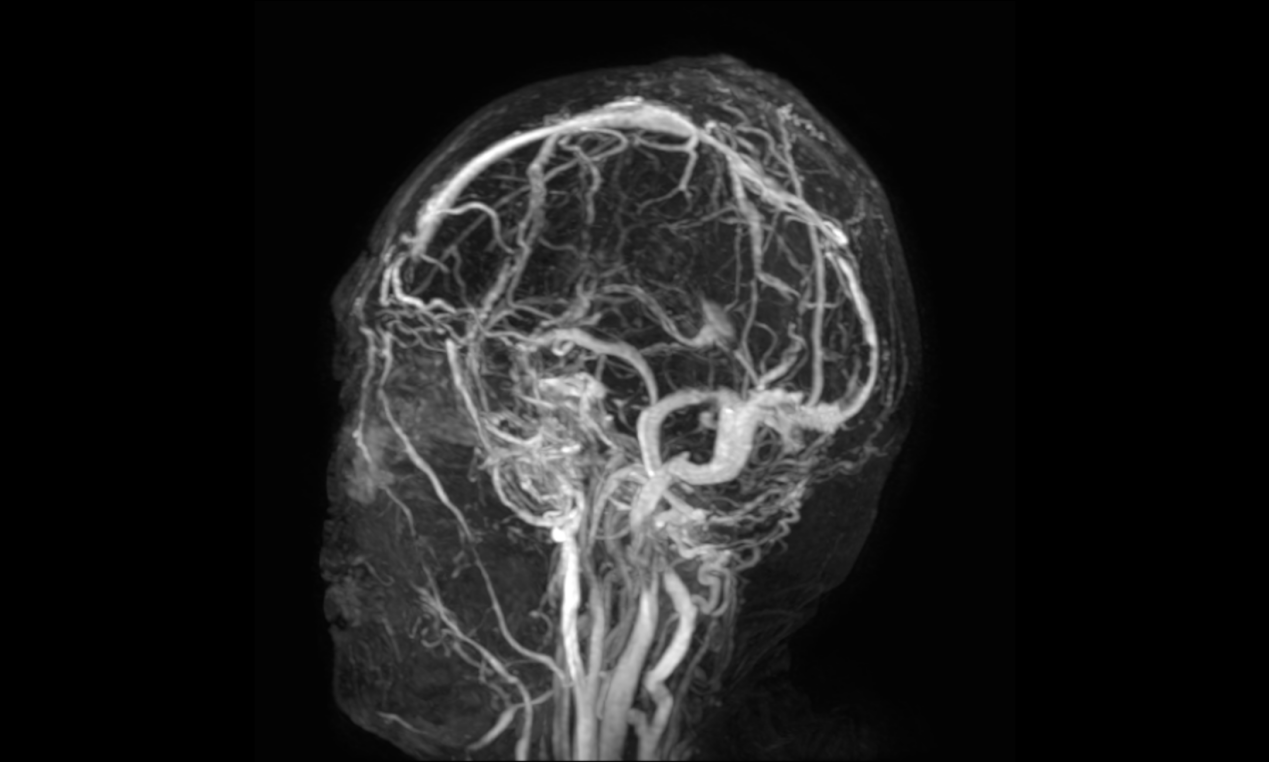

经过后期的综合治疗,患者恢复顺利,术后复查头颅磁共振显示重建的矢状窦血流通畅,目前患者已恢复正常生活。